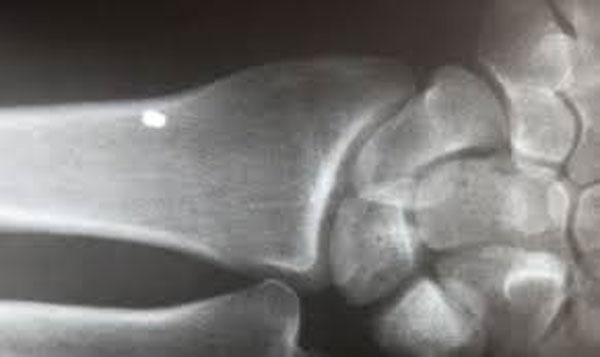

O doutor em química e física Alex Mosier examinou as amostras com Leir e afirmou ter encontrado fibras muito similares aos nanotubos de carbono, o que sugere que os fragmentos foram desenhados ou fabricados. Ele explica que “essas coisas não poderiam ser encontradas na natureza. Teriam que ser processadas, requerem uma engenharia complexa e não são fáceis de fabricar”. De acordo com Leir, as pessoas das quais esses objetos foram extraídos não possuíam cicatrizes visíveis nem sinais de inflamação, apesar de os raios x mostrarem a incrustação.